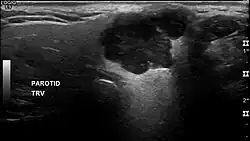

Pleomorphic adenoma in ultrasound

In terms of imaging studies, ultrasound can determine and characterize superficial parotid tumors. Certain types of salivary gland tumors have certain sonographic characteristics on ultrasound.[6] Ultrasound is also frequently used to guide FNA or core needle biopsy.